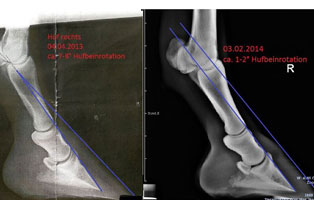

Die Diagnose sollte vom Tierarzt erfolgen und sichergestellt werden. Ein Röntgen sollte erfolgen, um den Schweregrad der Absenkung/Rotation des Hufbeines zu bestimmen. In schweren und unbehandelten oder falsch behandelten Fällen kann es zu einem Durchbruch des Hufbeines durch die Hufsohle und zum kompletten Ausschuhen kommen.

Durch die nun stark angegriffene Haltefunktion kann sich das Hufbein absenken, oder der Huf rotiert um das Hufbein. Beim Röntgen lassen sich hier die Winkel der Rotation/Senkung messen, bei schweren Fällen sind starke Veränderungen des Hufbeins erkennbar (Verformung, bis hin zur Auflösung!).

Foto von Tierärztin Karin Schmid – zeigt deutlich eingezeichnet das rotierte Hufbein vor (links) und nach (rechts) der Behandlung